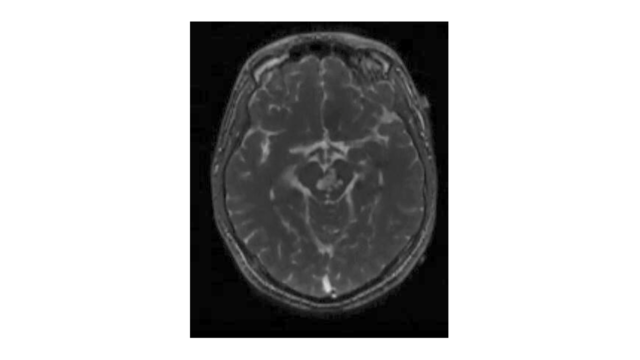

An 18-year-old male presented in 2009 with a six-year history of repeated hemorrhage from a brainstem cavernous malformation (Figure 5).

At his most recent presentation, he developed repeated episodes of temporary right hemiparesis and decreased fluency of speech. The lesion was removed via a lateral brain stem approach. The brain stem was opened using the midbrain entry site along the posterior half of the incision shown in Figure 4. The postoperative magnetic resonance imaging (MRI) of the case illustration is shown in Figure 6.